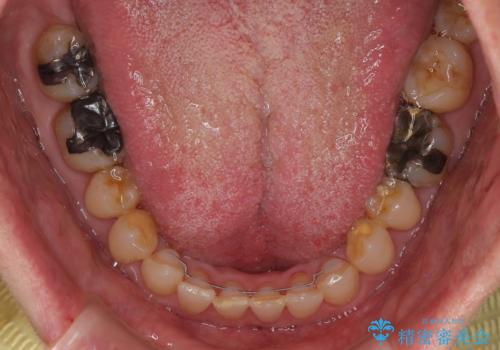

【モニター】ディープバイトで隙間の空いた歯列 ワイヤー装置での非抜歯矯正

下顎前歯が隠れるほどのディープバイトにより、強い咬合力と突き上げで上顎歯列に隙間が空いている状態でした。

手前に傾斜している奥歯をワイヤー装置で立ち上がらせ、咬み合わせの高さを挙上することで突き上げを解消し、空隙歯列を改善していくこととしました。

ディープバイトが改善され、睡眠時の食いしばりも緩和され、顎への負担が軽減されました。